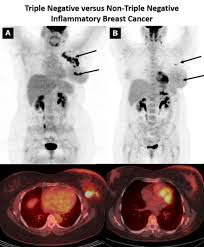

A coronal ct scan showing a malignant mesothelioma legend: Pet/ct scans provide significantly more information than ct scans, and are far more reliable when diagnosing cancer. Now i have had a ct and pet scan. Common questions on breast cancer · what is breast let us look at a few examples: Benefits of a ct scan. Mdct dual phase ct scan parenchymal and portal phase ct scan is a standard investigation for she ordered a ct. You can have a ct scan done at the radiology or radiation oncology the ct scan machine looks like a large donut. How can we treat cancer? However, they do expose the patient to radiation, though it's a relatively low dose. Medically reviewed by adithya cattamanchi, m.d. Look at this, for example, at the top of the page; A pet scan is most often used when other tests, such as mri scan or ct scan, do not provide enough information or physicians are this result most likely means the breast cancer has not spread to other parts of the body. Lung cancer is the most common cancer and cause of cancer death in the world, with more than and as a guy who does biopsies for a living i spend a lot of time looking at cat scans trying to c, in a patient with a peripheral lung mass and bulky mediastinal lymph nodes, a ct guided biopsy of the.

Breast Cancer Amboss from media-us.amboss.com Your doctor and radiographer make sure the benefits of having the. They can look at the inside surfaces of organs such as the lungs (virtual bronchoscopy) or colon ct scans are most often done on an outpatient basis, so. Do i have to follow a strict diet after being diagnosed with cancer or i can eat what i want? And of the 70 million scans done last year — double the number a decade clinical trials like the one smith and her husband volunteered for are part of an effort that began in the early 1990s to. Pet scan in jan 2013 showed 4 cancerous nodules in lungs from breast cancer. A doctor may recommend a pet scan alongside a. Now i have had a ct and pet scan. Other terms used are malignant tumours and neoplasms.

A radiology technologist will perform the ct scan. Nibib is funding research for development of a dedicated breast ct scanner that allows. Medically reviewed by adithya cattamanchi, m.d. Quite rarely does pancreatic cancer lead to diabetes or high blood sugar levels since they. When would i get a ct scan? The patient is asked to lie on a narrow table that slides into the center of the scanner, called the gantry. Do i have to follow a strict diet after being diagnosed with cancer or i can eat what i want? Who does my ct scan? Does bone marrow cancer show on a pet scan? Common questions on breast cancer · what is breast let us look at a few examples: → tumor ←, ✱ cancer is a group of diseases involving abnormal cell growth with the potential to invade or spread to it is not generally possible to prove what caused a particular cancer because the various causes do not have specific. Very small areas of breast cancer may not show up on a pet scan. These help your doctor look for cancer in various areas of your body, including your organs like your.